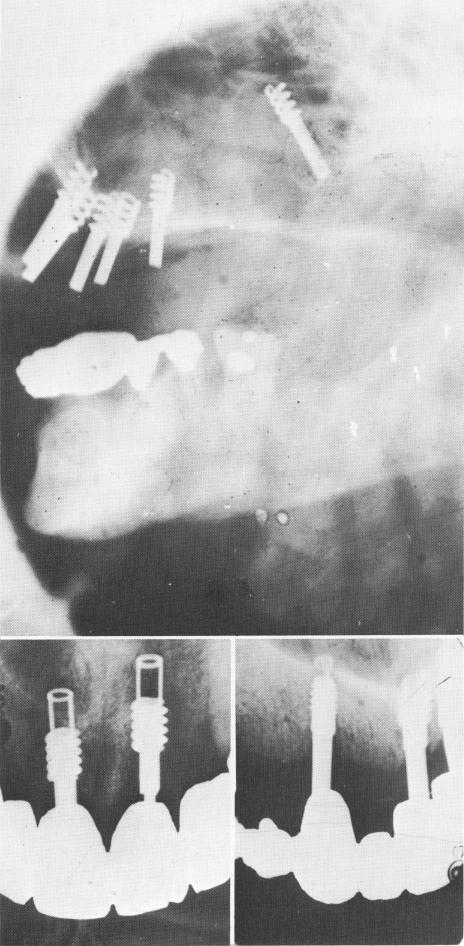

Fig. 14-12. A, A Chercheve type of spiral implant that was pushed into the maxillary sinus. It must be removed as quickly as possible. (From Linkow, L. I.: Alloplastic implants. In Goldman, H. M., Forrest, S. P., Byrd, D. L., and McDonald, R. E.: Current therapy in dentistry, vol. 3, St. Louis, 1968, The C. V. Mosby Co., pp. 335-356.) B and C, Radiographs showing various vent-plants perforating the nasal vestibulum.

Fig. 14-13. A, Pin implants are deeply embedded in the nasal vestibulum. B, A number of operative mistakes caused failure with the implants. The trephining of bone below the first implant perforated the mandibular canal. Also, the spirals were too close to the alveolar crest. A two- to three-spiraled implant should have been used insted of the four-spiraled one. (Arrow points to area of canal perforation.) C, Both helical burs penetrated the canal, causing temporary paresthesia. However, the most posterior implant was also set into the mandibular canal and had to be removed. D, The posterior implant was not firmly anchored because the underlying bone was overtrephined with the helical bur. In most situations where the canal is involved either by the instrumentation prior to the implant insertion or by the implant itself, a paresthesia is usually the result.